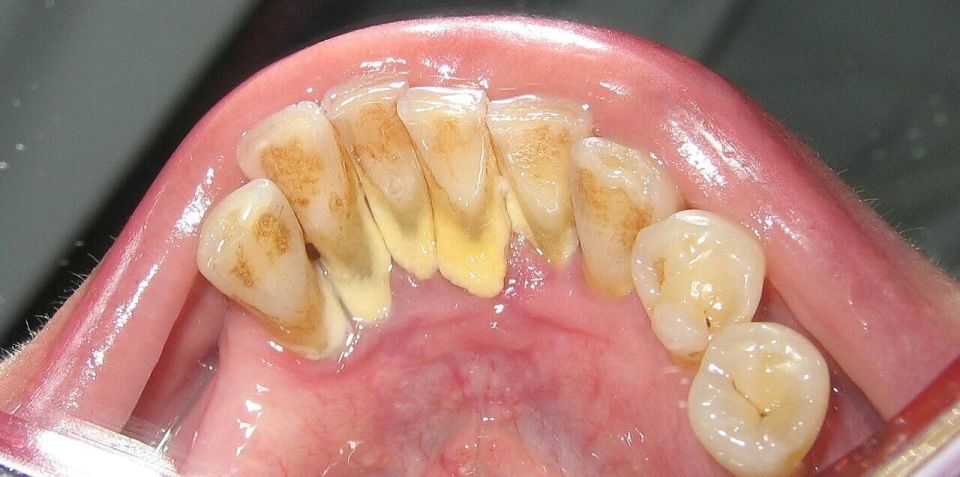

牙齿上的牙结石(牙根处黄色部分) 图源:wikipedia

当牙菌斑没有被彻底刷掉,它就会越积越厚。与此同时,它还会不断吸收唾液中的矿物质(尤其是钙、磷等元素),很快,它就开始“石化”,逐渐变硬。

严格意义上说,这就是牙结石的雏形。只不过在刚形成的时候,它还比较松散柔软,能通过认真刷牙、使用牙线清理掉。

一旦它完全钙化,那就相当于在牙齿上贴了一层硬壳,要完全去除靠普通牙刷根本无能为力。不过牙结石也不是不会掉,当牙结石持续增多,甚至很多医生都遇到过自称“牙齿碎了一块”的病人,其实碎下来的正是牙结石,确切说,掉下来的牙结石只是冰山一角罢了。

这也解释了为什么牙结石最容易出现在下门牙内侧、上后牙的外侧,这些位置都是唾液腺开口处,矿物质源源不断供应,堪称牙结石的“高产区”。